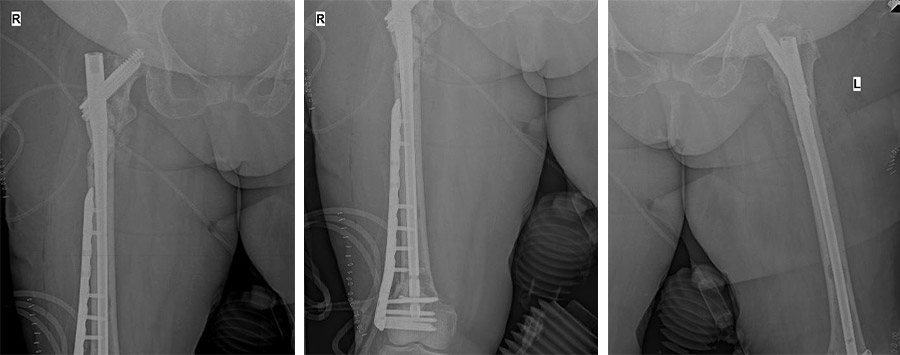

Postoperative: The X-ray shows open cleaning and cementation of the upper end of the right femur, followed by closed nailing of both femurs and an anatomical plate applied to the lower end of the right femur.